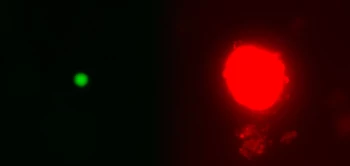

Onderzoekers van BPRC hebben een ontdekking gedaan die meer inzicht biedt in de ziekteontwikkeling van tuberculose (TB).

Bijna kwart wereldbevolking ongemerkt drager van bacterie Tuberculose is een infectieziekte waarvan de aanjager zich verspreidt via de lucht; deze Mycobacterium tuberculosis komt in kleine druppeltjes vrij wanneer een tuberculosepatiënt hoest....